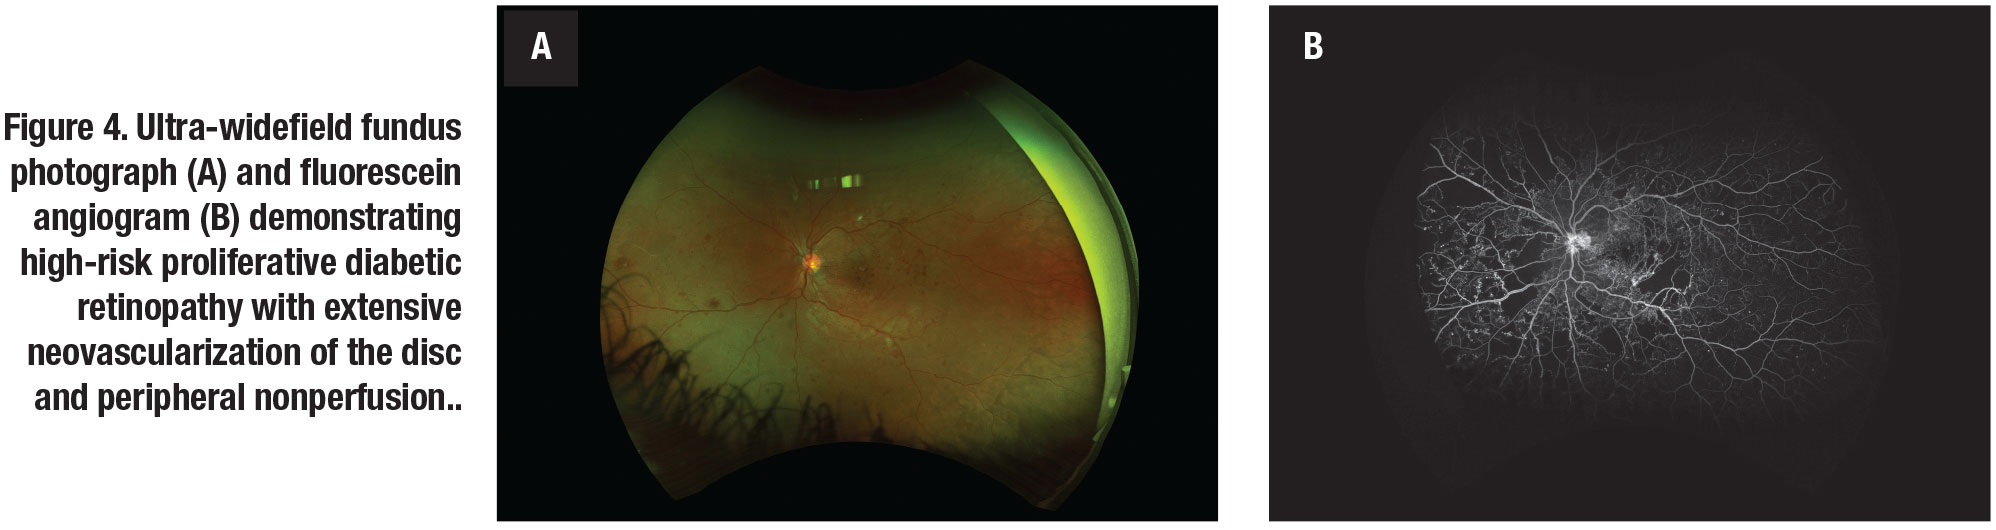

Ultra-widefield angiography has been shown to detect approximately four times more retinal non-perfusion and two times more neovascularization compared to conventional standard seven-field imaging (Figure 3, page 34). Additionally, UWFA detected non-perfusion and neovascularization in 10 percent of eyes that would have otherwise been missed by standard FA (Figure 4,).9

Reports of the association between peripheral non-perfusion and DME are conflicting. Some studies have reported a significant correlation between DME and peripheral retinal ischemia on UWFI. Matthew Wessel, MD, and colleagues found that eyes with retinal ischemia had 3.75-times increased odds of having macular edema compared to those without retinal ischemia.13